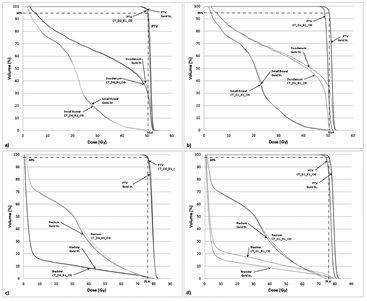

Differences between CT- and MR-based plans

The effects on uniform rED assignment on T2-based plans (T2_D1_B1_O0 and T2_D1_B1_O1) were found to be larger (figures 4(a) and (b)) than the Gold St. When optimization of the pancreas and prostate plans was performed, target coverage was achieved without violating OAR planning constraints; however this does result in larger/smaller difference in OAR doses compared with the Gold St (figures 4(c) and (d)). These large differences in IMRT plan quality metrics was partly due to changes in anatomical shape, volume and position of the organs/tissues in between image acquisitions (figures 5 and 6). However, the DVPs for the OAR still meet the planning criteria in table 1 for both pancreas and prostate IMRT plans (i.e. T2_D1_B1_O1 in tables 10(a) and (b)). The central axis (CAX) of the beams on the T2 images pass through different tissues (i.e. beams3 and 4 in figure 5 pass through different amounts of small bowel, large bowel and NST) with slightly different rED, shape and volume that lead to small changes in absolute dose, which yield very large percent changes compared to the Gold St. For example, panc2's stomach Dmax on the Gold St was 17 Gy and 52.2 Gy on T2_D1_B1_O0 (a +183.4% difference but still clinically acceptable). Optimization of the panc2 plan reduced the stomach Dmax to 51.9 Gy, which is within clinically acceptable limits but still a +178.8% difference. A similar observation was made on prost1, where the bladder Dmean on the Gold ST were 9.2 Gy but increased to 12.7 Gy (+37.7% difference) on T2_D1_B1_O1. Re-optimization on the T2 reduced the bladder mean dose to 9.62 Gy, which is clinically acceptable but still 4.1% higher than the Gold St. Additional examples of large increases in DVP that remain within clinical acceptable range in table 1 include the 6% increase in rectum V45, which is a difference of 22.5% and 28.6% between Gold St and T2_D1_B1_O1, respectively.

Figure 4. Pancreas (panels (a) and (b)) and prostate (panels (c) and (d)) IMRT with 1.5 T field dose volume histogram for a representative case planned on MRI T2. Note: figures 4(b) and (d) contain DVH curves for the re-optimized plan on the T2 dataset.

Even though it is difficult to isolate the effects of anatomical changes to assess its impact on plan quality; however, it is useful to investigate the combined impact of uniform rED and magnetic field on T2-based plans since the use of MRI in treatment planning with combined MRI and radiation delivery systems. Larger dose differences were found on the unoptimized T2-based plan (table 10 and figures 4(a) and (c)), where variations in PTV coverage were within 5% of the Gold St and DVP differences for OAR could be larger than 5%. These larger dose differences in OAR were partly due to anatomical changes occurring during the time between the CT and T2 image acquisition. Acceptable plans meeting dose-volume criteria (table 1) could be obtained through plan re-optimization based on T2 images (figures 4(b) and (d)), which used the same IMRT constraints from the Gold St without changing the beam orientation. The PTV was subsequently rescaled so that 95% of the PTV volume received the prescription dose, which reduced the variation in PTV plan quality DVPs to <2.0%. The use of another cost function could create a 3D dose distribution that was comparable to, if not better, than the Gold St. Performing the optimization without any changes to the plan demonstrates that the planning system could come up with an acceptable dose distribution meeting the criteria in table 1 despite that fact the OAR had shifted in position and changed in volume/size between the time of CT and MRI acquisition These differences in anatomical shape, volume and position between image acquisition times are necessary to consider in RT planning and similar establishment control methods (similar to our institutional) to reduce these differences between the two image sets is important (Paulson et al 2015).